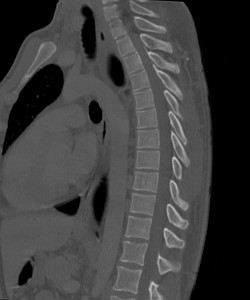

Грудной отдел позвоночника